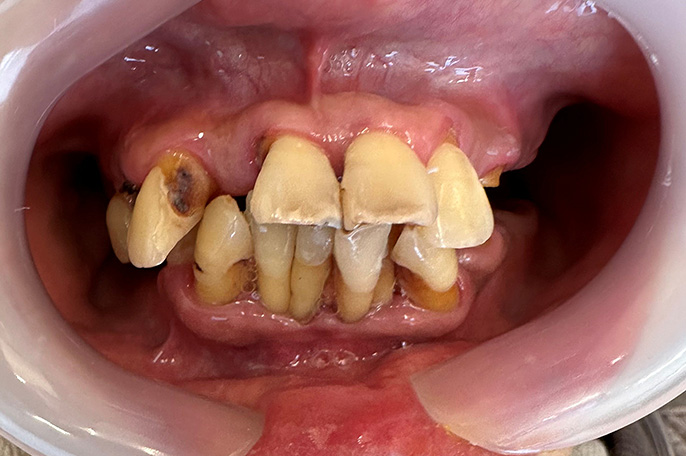

オールオン4 症例・56歳男性主訴:上下の主訴:歯がボロボロで食事ができない。

口の中がボロボロで噛めなくて困っている患者さんです。上下ともにオールオン4治療で、上下4本ずつインプラントを入れて即日で仮歯まで装着しました。

| 治療期間 | 6ヶ月 |

|---|---|

| 治療費 | 5,000,000円(税込) ※施術代、インプラント、被せ物、CT全て込み |

| メリット | 即日で抜歯して仮歯まで入るので一気に改善することが可能です。従来の治療だと1年以上かかるところを6ヶ月程度の治療期間で終えることが出来ました。 |

| デメリット | 外科処置を伴います。 |

| 起こりうる症状 | 外科処置後に腫れ、痛みが出ることがあります。セラミックが破損する可能性があります。 |

術前

術後